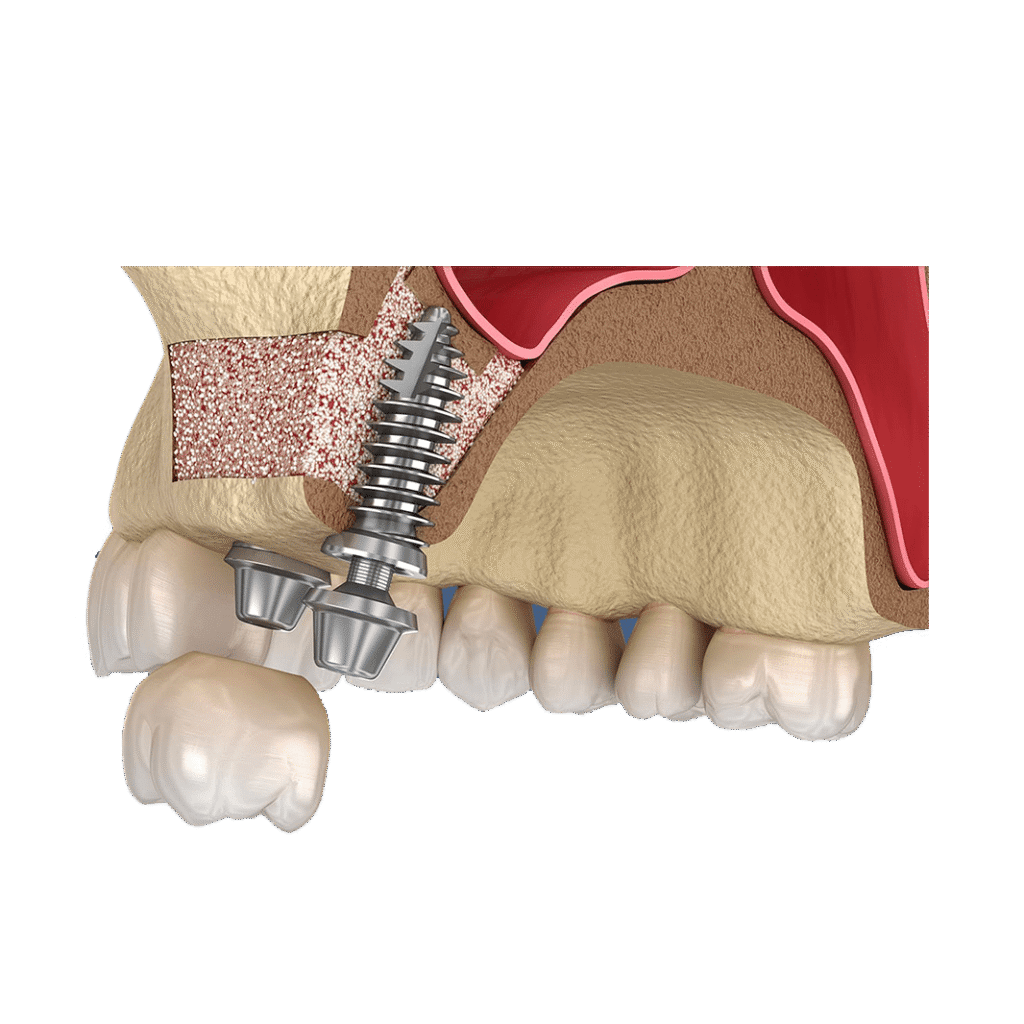

그리고 나서 저희 병원에서 치조골 이식을 받으신 후

직경이 굵은 임플란트를 식립하는 수술을 받으신 케이스입니다

아래 그림은 임플란트 제거후 3개월이 지난다음

재수술을 한 케이스 입니다

주변에 본택이라고 하는 부분이 보이는데요

이런 부분은 골이식을 하고 직경 5.0이상의 임플란트를 식립하였습니다

골이식 부분을 차폐막이라는 걸로 고정을 한 술식입니다

치조골 이식에서 상당히 많으 쓰이는 부분인데요

임플란트 제거후 치조골 이식술과 직경5.0임플란트 재식립

임플란트 제거후 치조골 이식후 5.0 직경의 임플란트를 재수술 하였습니다

전후 사진을 보면 확실히 직경이 달라진걸 느낄 수 있습니다